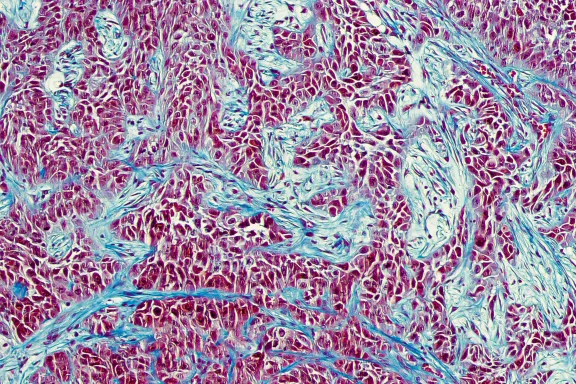

• Cette image est issue des travaux de recherche de l'équipe de Salvador Aznar Benitah, lauréat du Prix Liliane Bettencourt pour les sciences du vivant 2020.

©Alexandre Darmon/Art in Research pour la Fondation Bettencourt Schueller